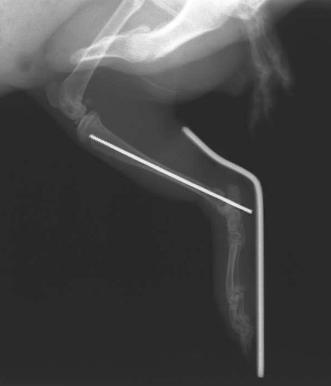

レントゲン検査を行うと、頸骨遠位端骨折を起こしていました。

整復はキルシュナーピンを挿入しましたが、一番細いピンしか入らず 強度が低いため

また旋回防止を目的として外固定も実施しました。